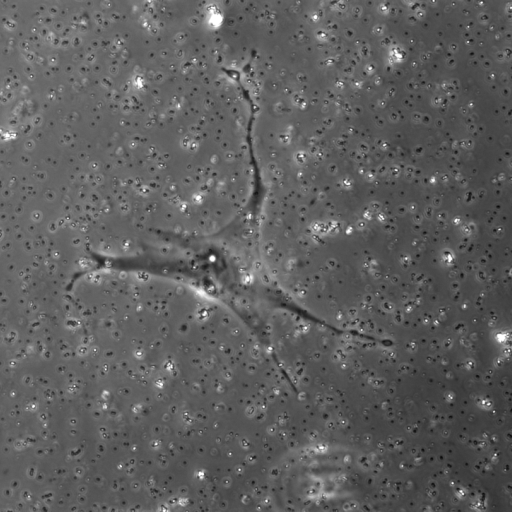

We evaluate the performance of each approach with five classical metrics: intersection over union (IoU), Dice score, precision, recall, and Hausdorff Distance (HD). We provide results on datasets , , and in Tables 1, 2, and 3, respectively. In Figure 2, we also illustrate representative segmentation results on dataset for each methods.

Raw

The original U-net model produces poor segmentation results on datasets and while performing better on dataset . CE-net performs better than U-net and results in a strong recall in all three datasets. Attention U-net outperforms both CE-net and U-net on most metrics. The Attention gates incorporated in AURA-net allow outperforming CE-net, while its pre-trained layers help improve over Attention U-net. On top of that, the AC loss provides the network with additional information on object regions. As a result, AURA-net generally outperforms competing approaches. It occasionally scores closely to Attention U-net and CE-net, and even concedes a lead on recall in datasets and and on precision in dataset . It however performs best overall, with a consistent clear advantage on the IoU, Dice, and HD metrics.

In Figure 3, we illustrate failure cases in dataset . In the first example, AURA-net fails to correctly segment the bottom part of the object. This outcome is unsurprising considering that the raw image exhibits a lower SNR than any of the training data. In the second example, the segmentation mask predicted by AURA-net contains several objects, yielding a poor overlap with the ground truth annotation featuring a single cell. However, the original image reveals the presence of a second, partially cropped non-annotated cell. In this case, part of AURA-net’s “false” detection are actually correct predictions that have been omitted in ground truth annotations.